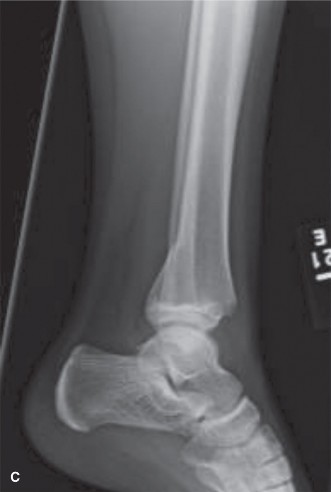

Tillaux fragment. Coincidentally, a 13-year-old male (a player for the opposing team) is in the next bed in the emergency room, awaiting evaluation of a left ankle injury that was sustained in a similar fashion later in the game. Upon your evaluation, his skin is closed, his foot and ankle are swollen, and he is able to actively flex and extend his toes with minimal discomfort. His initial radiographs are shown ( Fig. 10–15A** –** C ). Based on the available imaging you diagnose this patient with a (choose the correct group of answers).

Figure 10–15 A–B

Figure 10–15 C

The correct answer is (B). Classically, triplane fractures have the radiographic appearance of a Salter–Harris II fracture on lateral radiographs and of a Salter–Harris III fracture (this is the Tillaux fragment) on coronal imaging.